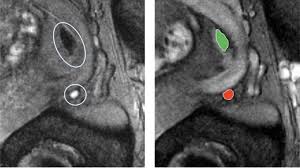

Diagnosis Of Transition Zone Prostate Cancer By Multiparametric Mri Added Value Of Mr Spectroscopic Imaging With Slaser Volume Selection Journal Of Biomedical Science Full Text

Diagnosis Of Transition Zone Prostate Cancer By Multiparametric Mri Added Value Of Mr Spectroscopic Imaging With Slaser Volume Selection Journal Of Biomedical Science Full Text from media.springernature.com